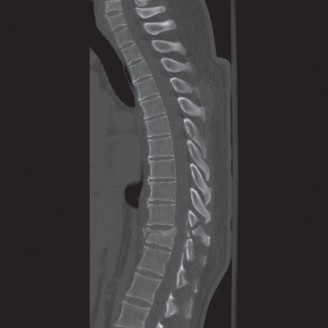

In addition to MRI, a fine-cut computed tomography (CT) scan is essential for evaluating bony destruction. CT allows the surgeon to assess bone stock for pedicle screw purchase and to template the size of the interbody cages required for anterior column reconstruction. Upright standing radiographs (if the patient can tolerate them) or full-length supine films are necessary to evaluate global spinal alignment and regional kyphosis.

Phase 3: Long-Term Follow-Up and Functional Restoration (Months 3–12)